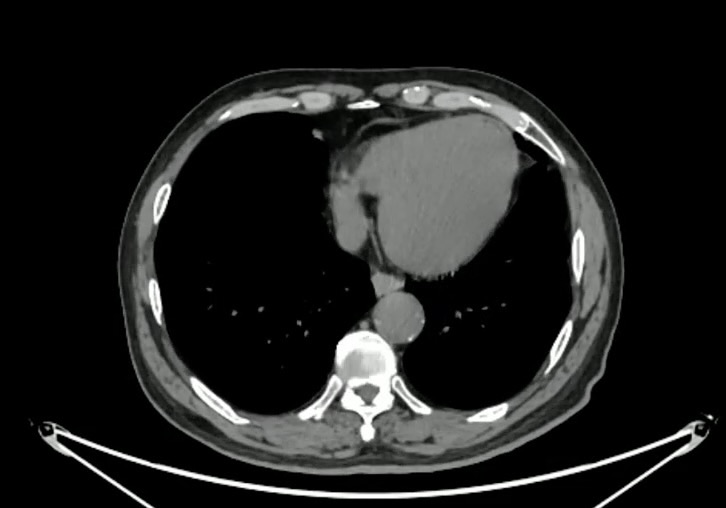

病例【腹盆】结肠双曲占位之脾曲占位,男,63岁,腹痛7天,便秘十余年,一般3-4天大便一次

【患者信息】:男,63岁。

【主诉】:腹痛7天。

【现病史及既往史】:便秘十余年,一般3-4天大便一次。

结肠癌 (170)